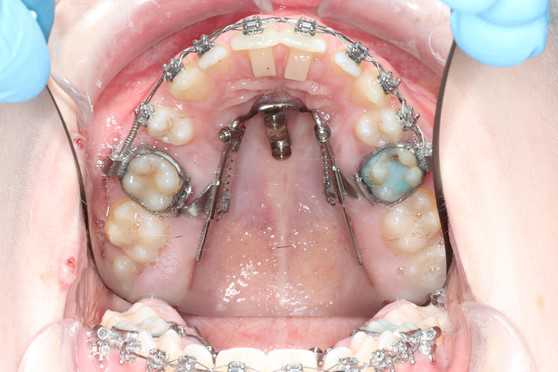

Bruges til at udvide ganen.

Den limes fast på tænderne. Der skal skrues i midten af bøjlen, I får en grundig instruktion på tandreguleringsklinikken.

Der kan opstå lidt spænding ved tænderne, næsen og evt. mellem øjnene.

Ofte kommer der et mellemrum ved fortænderne i en periode.